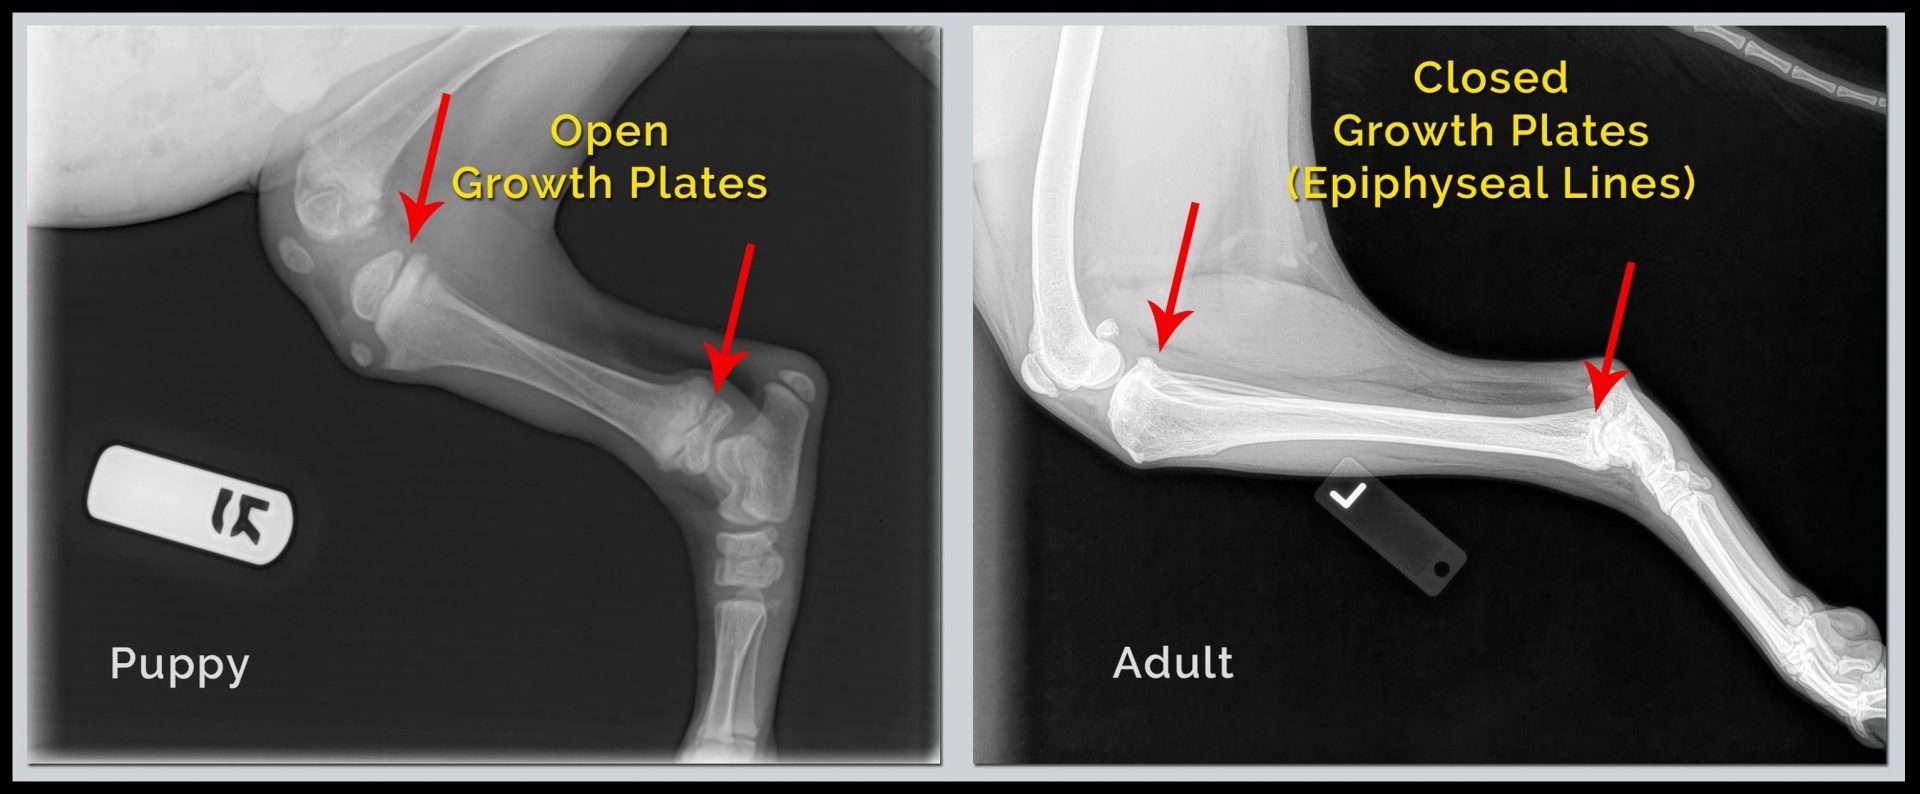

As a young animal grows so must its bones grow. Where does creation of new bone that allows long bones to lengthen as the animal grows take place?

Epiphyseal plates.